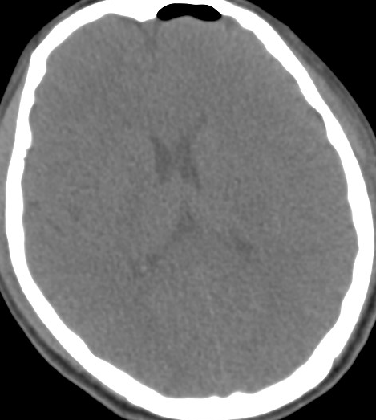

2014-9-29 CT

2014-10-5 CT